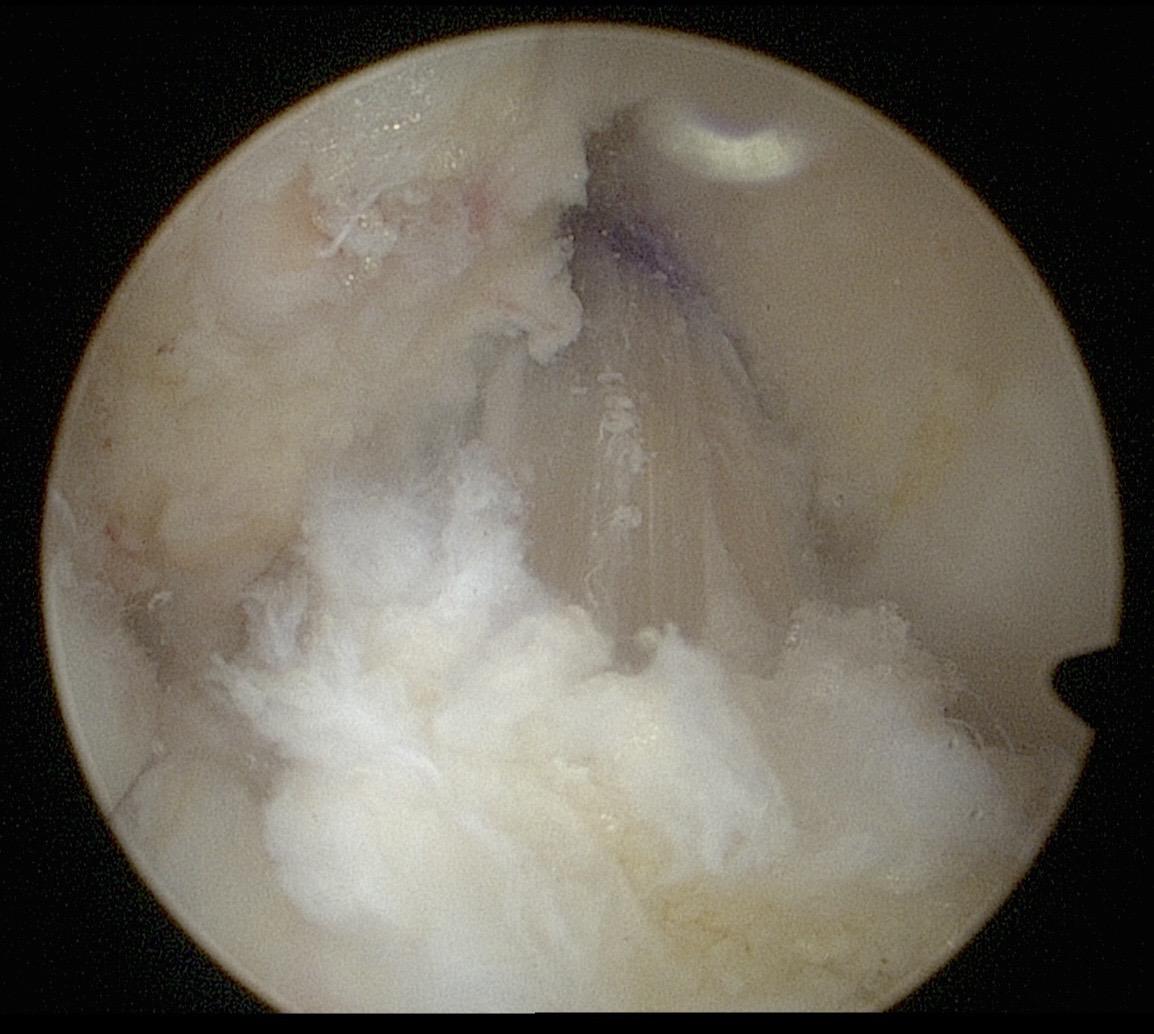

前交叉韧带重建。面对前交叉韧带的断裂,我们选择重建。希望这根强大的移植体,能为他撑起一片天,让他再次在运动场上放飞自我。前交叉韧带重建 前交叉